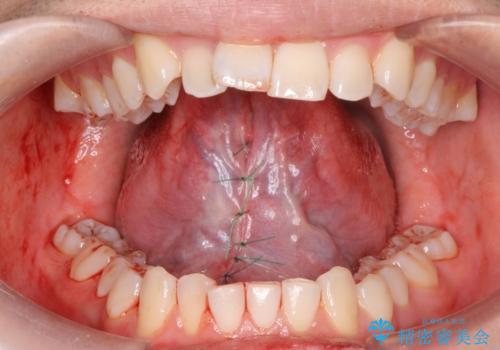

- 英語の練習をしていて舌が動かしにくいとの事で来院。

舌小帯切除術を行い舌の可動域を広げました。

- 舌小帯切除術 3.3万円費用は治療当時の料金となります